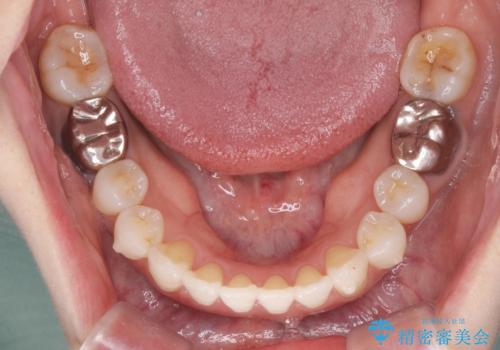

抜歯をせず前歯の角度を改善するマウスピース矯正治療

治療期間が約半年で行うことができ、歯を抜かずにマウスピース矯正で可及的に前歯の角度を改善する治療方針を

奥歯の状態等も鑑みて選択されました。

約半年で大きく前歯の角度を改善することができ、抜歯を行わない矯正治療の結果に大変喜んでいただくことができました。